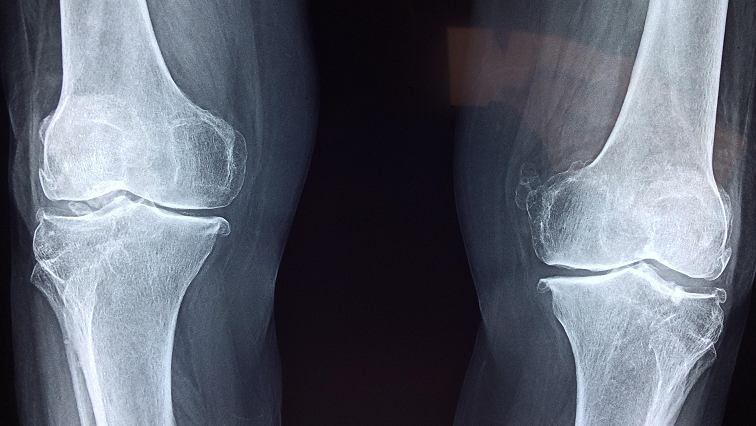

With an ageing population, sport injuries and obesity among the causes, the rate of joint replacement surgery is increasing at a rapid rate. Currently more than 85,000 hip and knee replacements are undertaken each year in Australia. The outcomes of joint replacement are variable.

“This new 3D bioceramic scaffold embedded with silver-gallium (Ag-Ga) liquid metal nanoparticles offers a dual-function biomaterial that simultaneously combats persistent infection and promotes bone regeneration,” says Flinders University Associate Professor Vi-Khanh Truong, lead author of a new article in Advanced Functional Materials.

“In our latest research we show our scaffolds significantly reduce bacterial colonisation at implant sites and promote healthy bone integration, confirming both antibacterial efficacy and regenerative capability in a physiologically relevant setting.”